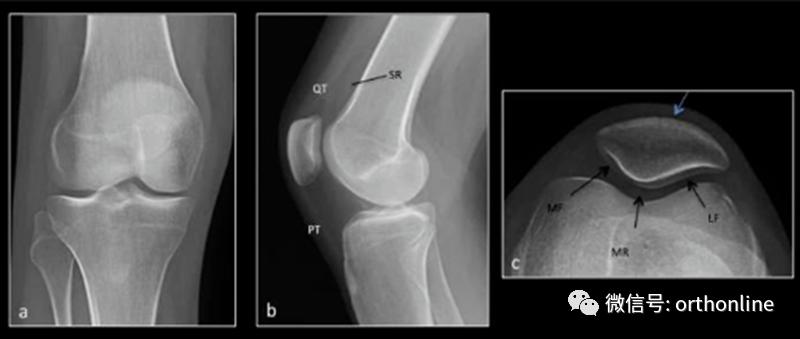

常见影像学检查包括X线、CT和MRI检查。X线早期无异常,直到晚期阶段,如出现广泛的软骨丧失、关节间隙丧失及相关的软骨下骨硬化和囊性变化,X线可诊断。MRI是非侵入性诊断方法,有望在肉眼可见的形态学软骨损失之前检测软骨病变以及软骨内部紊乱的独特功能。

正常X线 a.膝关节正位 b.膝关节侧位 c.髌骨轴位

髌骨软骨软化平片及CT表现:膝关节侧位片示关节间隙变窄, 关节缘皮质线有中断。CT示髌股关节略有错位,关节间隙变窄,软骨下骨质密度增高